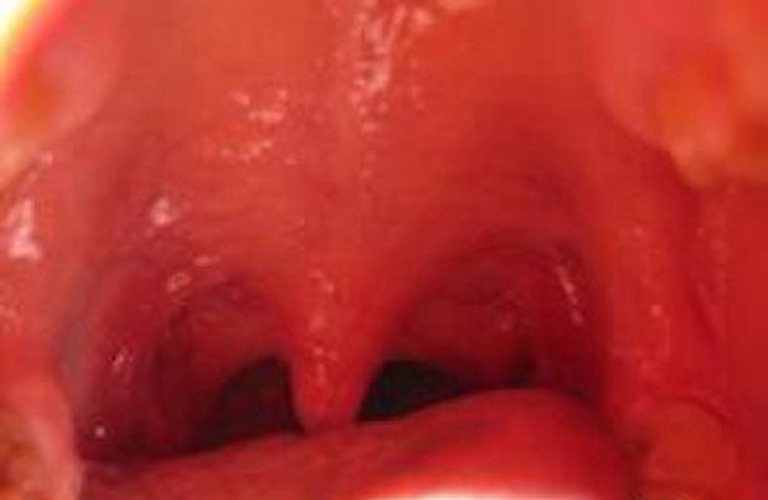

急性咽喉炎圖片

急性咽炎多表現為咽部發乾